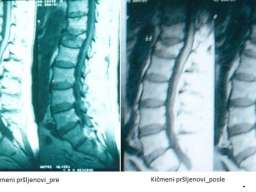

• posebno efikasno obnavljanje hrskavice – jedinstveno u svetu.

• degenerativnih koštano-zglobnih oboljenja i povreda (obnavljanje međuzglobnog prostora kičmenih pršljenova; obnavljanje zglobnog prostora kuka; obnavljanje zglobnog prostora kolena; zarastanje komplikovanog preloma pršljena; zarastanje preloma drugih kostiju; obnavljanje potpornog tkiva zubâ u slučajevima paradontopatije);